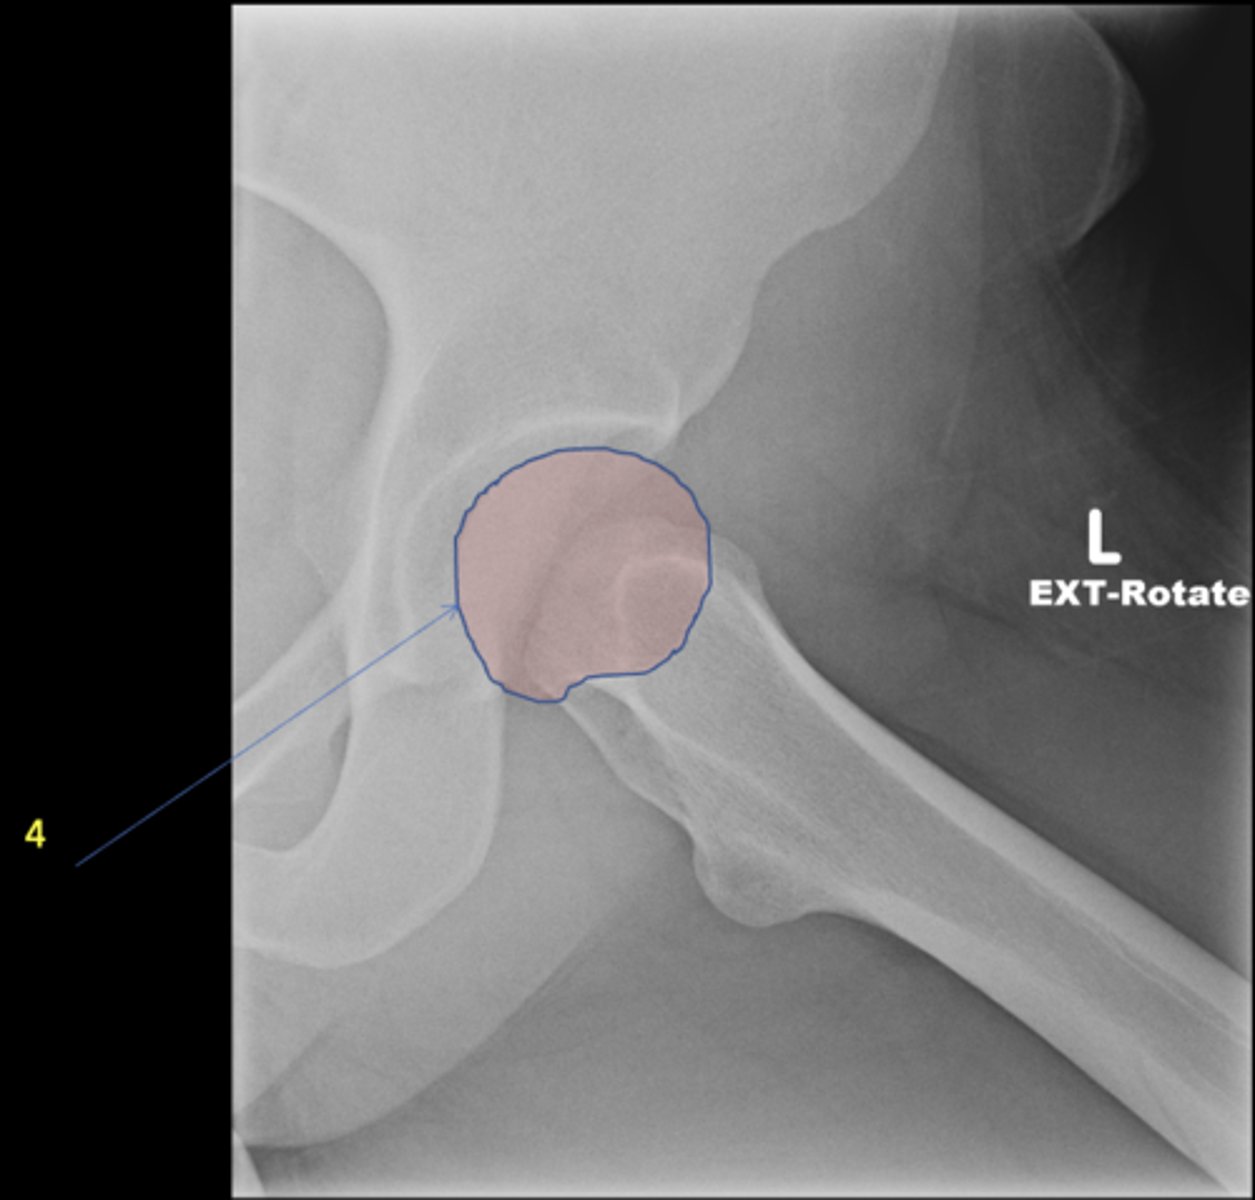

Left AP hip

View?

Phleboliths

ID 1

Obturator foramen

ID 2

Kohler's teardrop

ID 3

Gluteus medius

ID 4

Ischial tuberosity

ID 5

Acetabulum

ID 6

Anterior inferior iliac spine

ID 8

Lesser trochanter

Greater trochanter

ID 9

Sacroiliac joint

ID 10 (joint)

Sacrum

ID 11 (bone)

ID 12

Anterior superior iliac spine

ID 13

Left frog-leg hip

Femoral head

Ischial spine